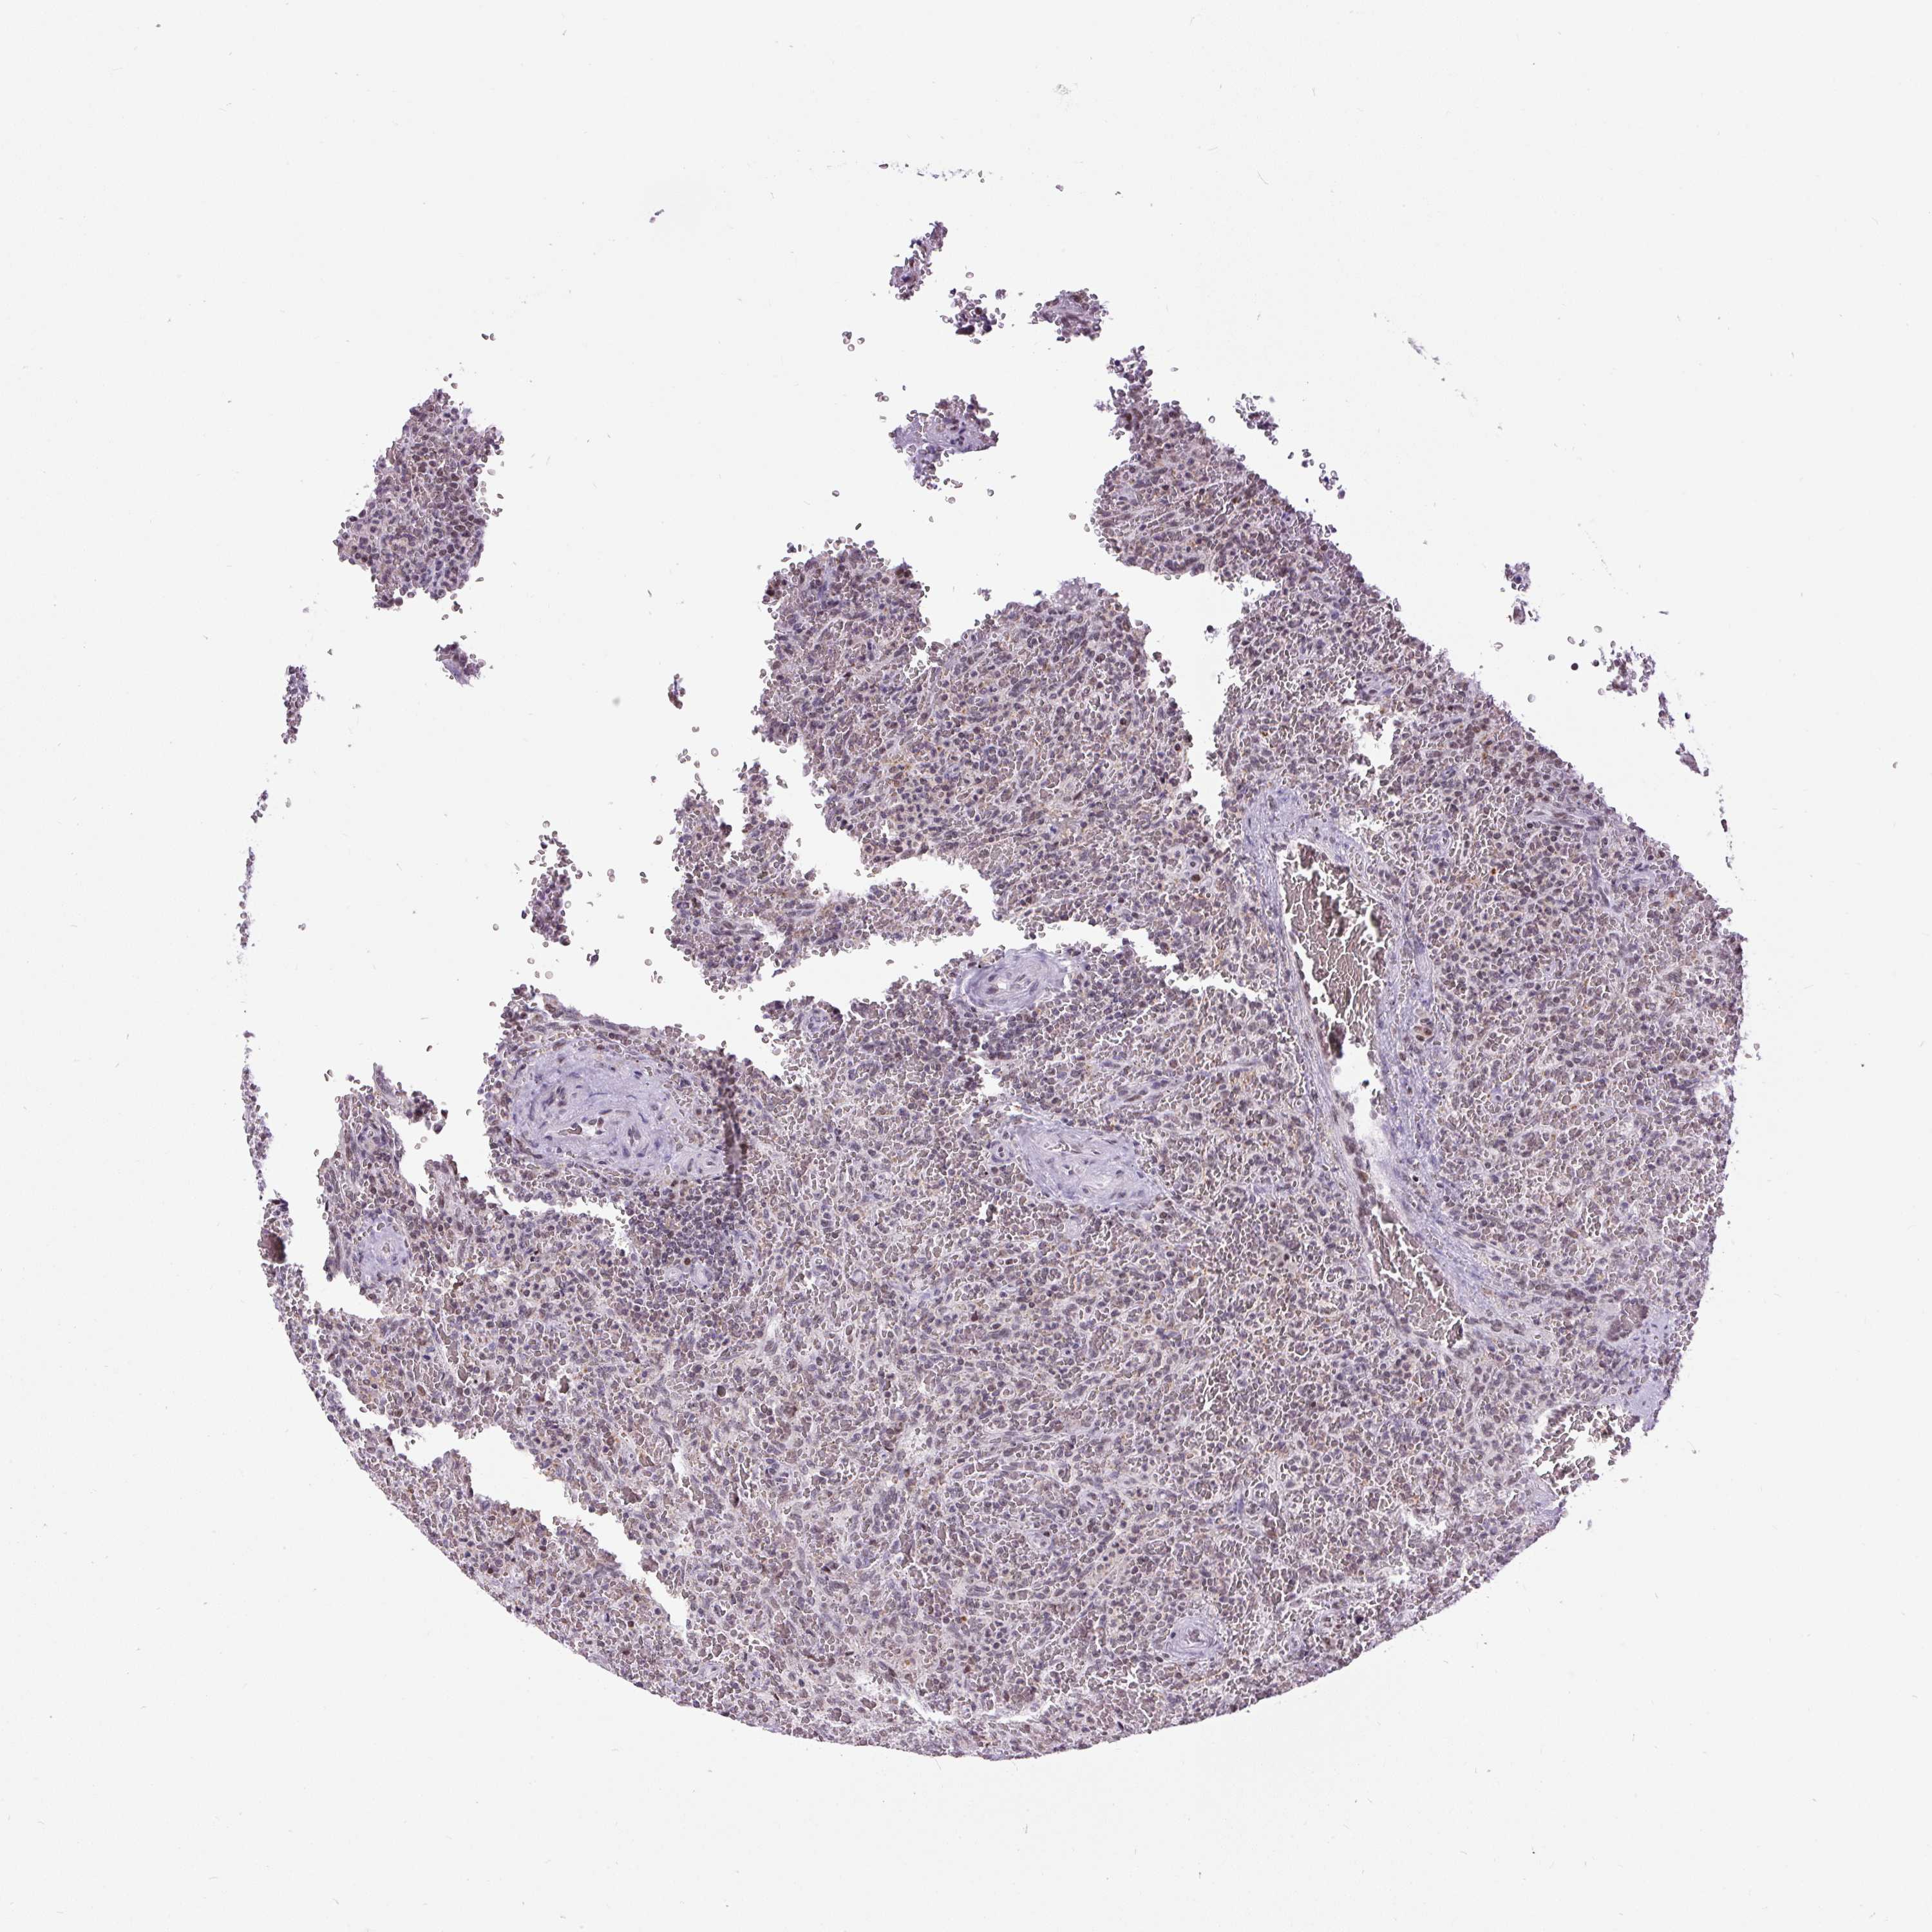

LYMPHOMA - Protein expressioni

A mouse-over function shows sample information and annotation data. Click on an image to view it in a full screen mode. Samples can be filtered based on level of antibody staining by selecting one or several of the following categories: high, medium, low and not detected. The assay and annotation is described here.

Each image is clickable and will lead to virtual microscopy that enables deeper exploration of all samples and also displays staining intensity scores, fraction scores and subcellular localization as well as patient and tissue information for each sample.

Antibody HPA055779

Staining

High

Medium

Low

Not detected

Intensity

Strong

Moderate

Weak

Negative

Quantity

>75%

75%-25%

<25%

None

Location

Nuclear

Cytoplasmic/membranous

Cytoplasmic/membranous,nuclear

Malignant lymphoma, non-Hodgkin's type, High grade